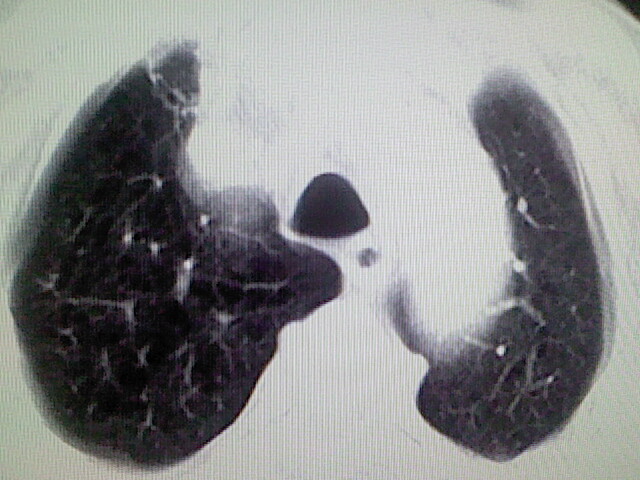

以下是引用zsl6918在2008-8-28 16:49:00的发言:[br]双肺炎性病灶,食管狭窄估计与心房增大压迫所致。

以下是引用xulianj在2008-8-28 20:36:00的发言:[br]慢支肺气肿伴感染,右上肺陈旧性结核;食道建议胃镜检查。

以下是引用wqs571018在2008-8-28 21:18:00的发言:[br]慢支继发感染,右上肺陈旧性结核;食道建议胃镜检查。